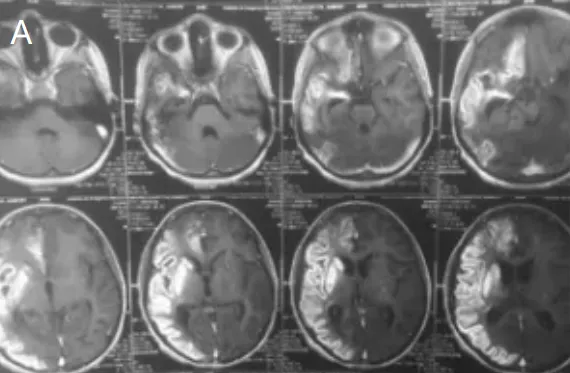

在深入诊查后,医学影像学的答案出现了——一张脑血管造影图像清晰地呈现了小宇脑内血管的真实面貌。影像中显示,小宇的双侧颈内动脉末端和大脑中动脉开口处出现了异常的血管闭塞,同时大量细小的异常血管网络在脑内形成,这种现象在医学上被称为"烟雾病"。

烟雾病是一种极为罕见的慢性闭塞性脑血管疾病。这个名字的来源很有趣——因为在脑血管造影图像上,这些异常增生的细小血管看起来就像烟雾一样弥漫在脑部。与成人患者多表现为脑缺血性卒中不同,儿童烟雾病患者通常以慢性反复头痛、肢体无力、癫痫等缺血症状为主要表现。更严重的是,长期的脑缺血会逐步影响儿童患者的认知发育和智力水平,国际研究数据显示,部分烟雾病儿童患者会出现不同程度的智力受损。